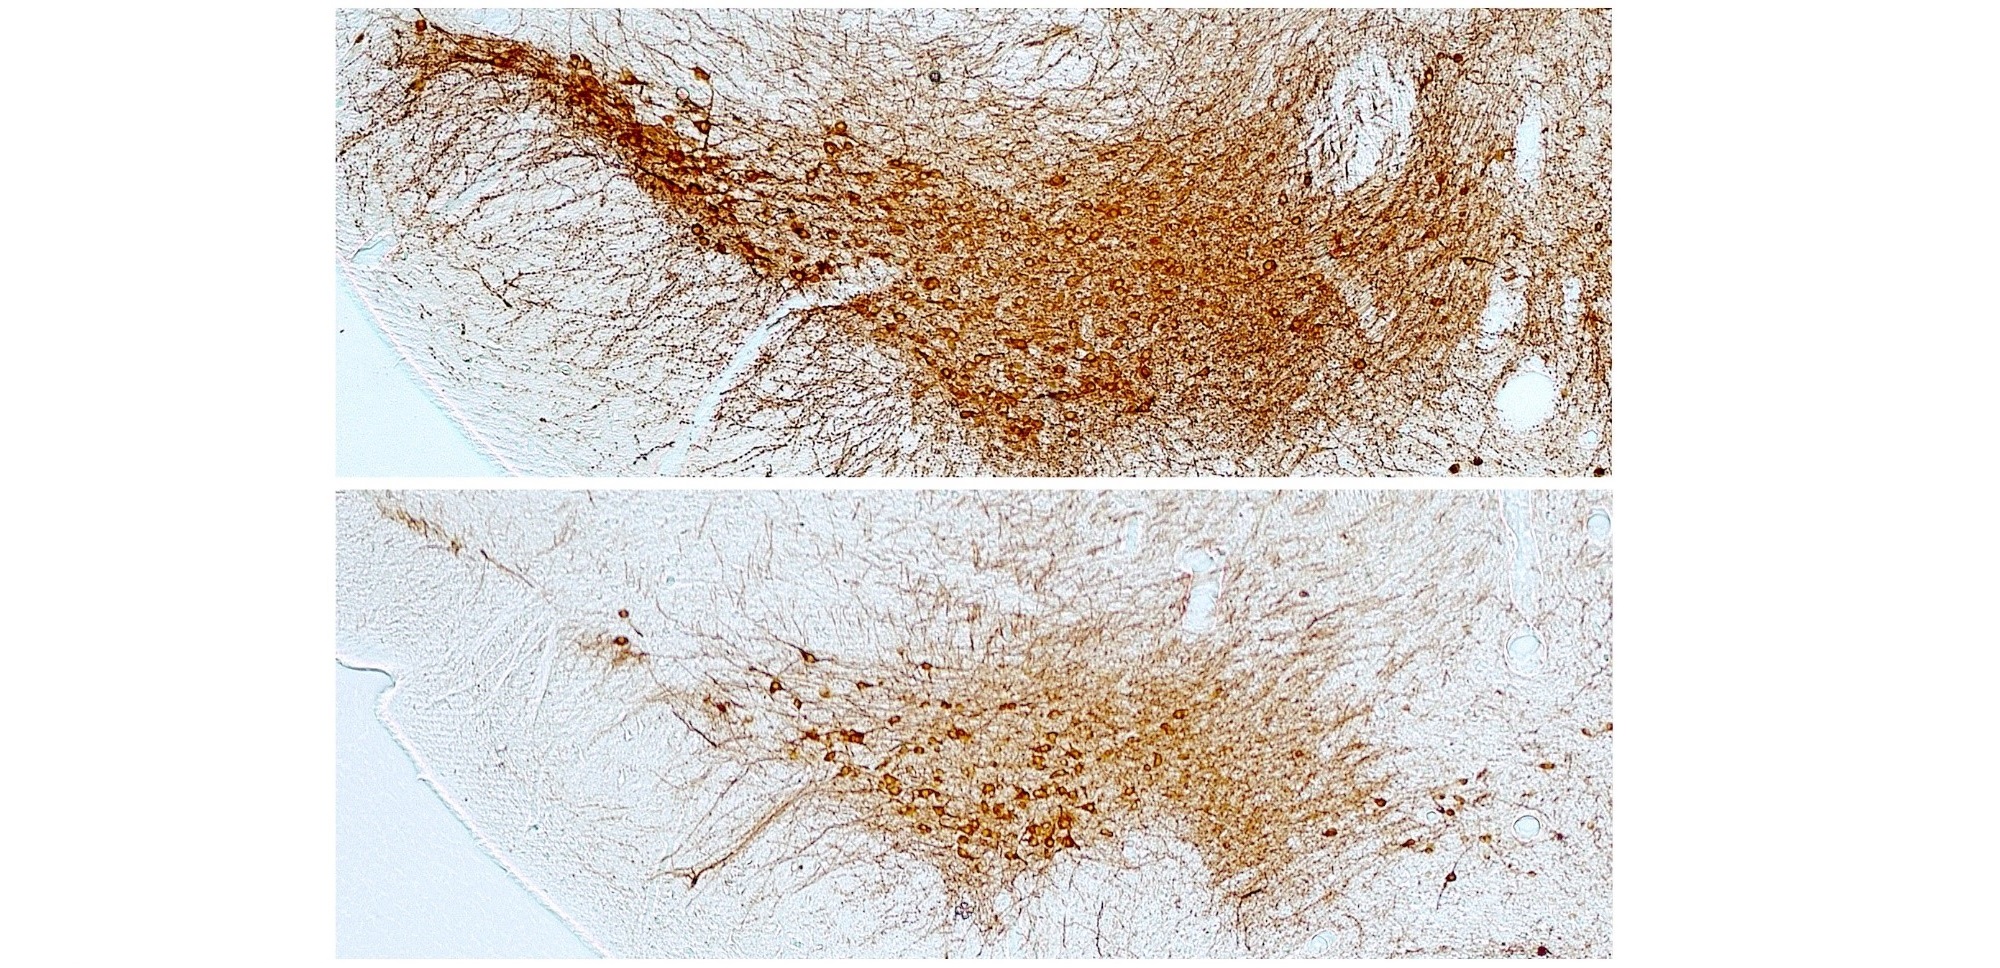

Diseño y ensayo pre-clínico de una nueva molécula para la enfermedad de Parkinson

26/08/2020